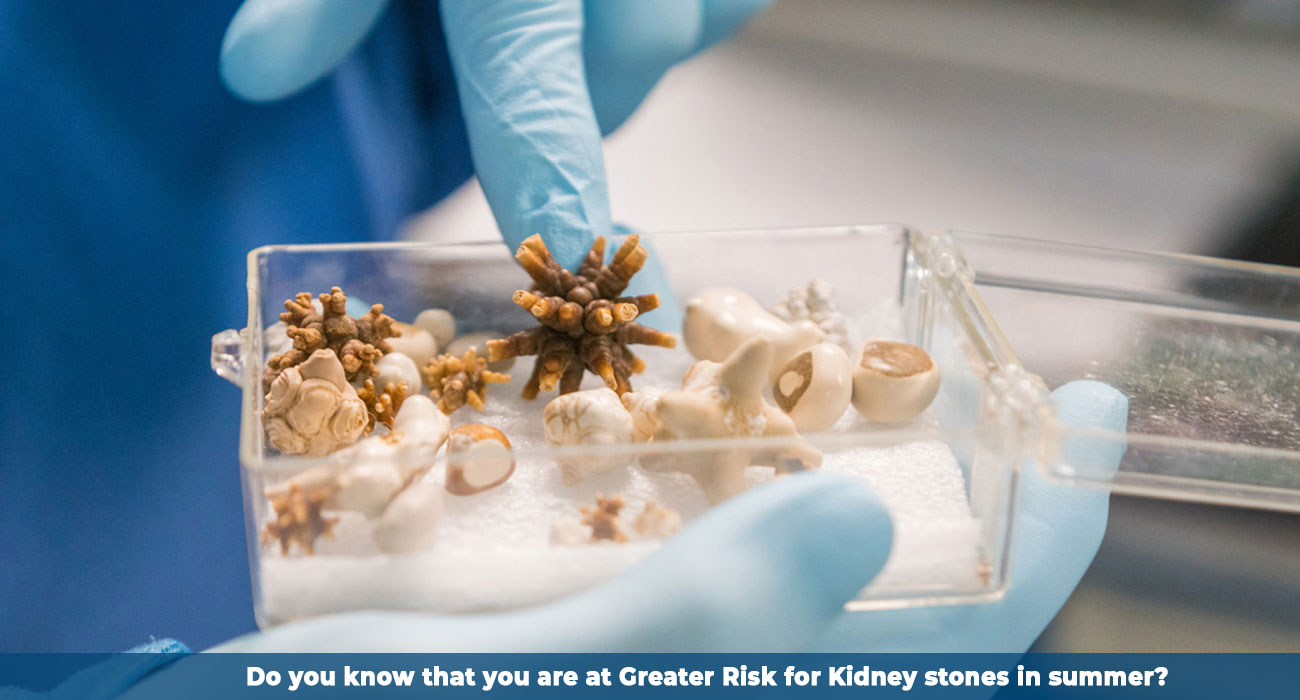

Kidney Cancer Surgery: Partial vs Radical Nephrectomy Explained

Kidney cancer treatment often involves surgery; however, one of the most critical decisions patients and doctors face is “choosing between partial nephrectomy and radical nephrectomy.”

How Is Robotic Partial Nephrectomy Changing Kidney Tumor Treatment?

Kidney cancer stands as the 16th most common cancer globally. When someone first hears the words “You have a kidney tumor,” the world seems to pause for a moment.